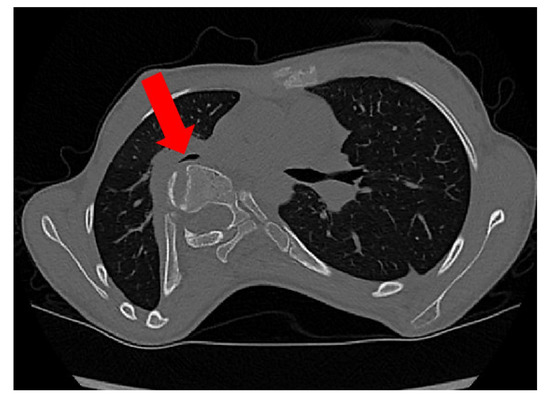

- Sagittal diameter and sternovertebral distance: These are two parameters for measuring the sagittal depth. The sternovertebral distance is the anterior–posterior distance between the posterior midpoint of the sternum and the anterior point of the apical vertebra [21]. The sagittal diameter is the anterior–posterior distance between the posterior midpoint of the sternum and the anterior point of the foramen. Both are measured on an axial CT scan. Takahashi et al. [22] report a significant negative correlation between the sagittal diameter and spine curvature. Measurements of the sagittal depth have been used to evaluate pre- to postoperative differences [21]. It has been shown that the sagittal diameter, as well as the sternovertebral distance, significantly decreases after spinal fusion surgery [21]. The sagittal diameter has also been used to evaluate the effect of thoracic deformity on pulmonary function [22].

- Spinal intrusion ratio: This parameter represents the sagittal intrusion of the thoracic spine into the chest and has been demonstrated to be related to the size of the airways [5,23]. SIr is the ratio between the distance from the anterior vertebral column contour to the interior contour of the convex ribs and the distance from the internal sternal surface to the anterior contour of the vertebral column.